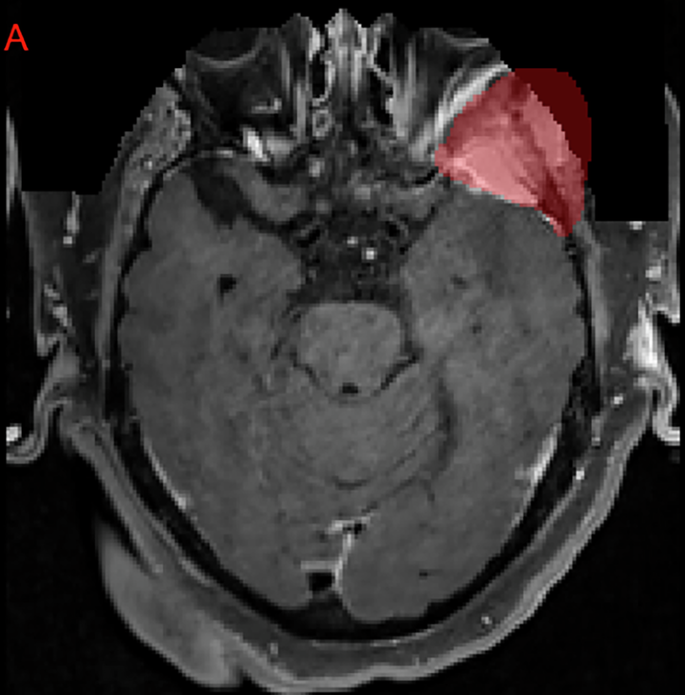

The imaging dataset includes exclusively 3D T1c brain MRI scans in native acquisition resolution in either the intact (Fig. 1) or postoperative setting (Fig. 2, 3), which mimics the data available for most radiotherapy planning. While additional sequences such as T1-weighted, T2-weighted, T2-FLAIR, and computed tomography are sometimes used in clinical workflows, these were not consistently available nor required for RT planning at all centers and were therefore not included in the dataset.

Panels A, B, and C depict a left anterior falcine meningioma (red) on axial, sagittal, and coronal images respectively. Panel B demonstrates an area of hypointense encephalomalacia between two separate anterior falcine meningioma components. Panels B and C highlight the defacing process, which removes pixels in and around the face to eliminate potentially identifying facial features.